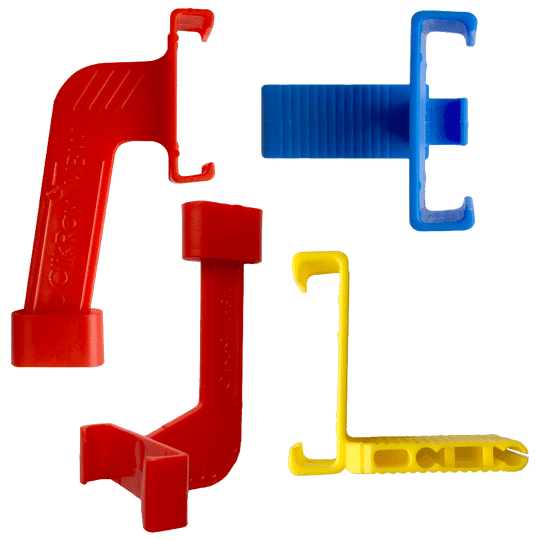

Sizes:

Size 1 blocks are for Size 1 child sensors (Approximately 20 mm x 30 mm)

Size 2 blocks are for Size 2 adult sensors (Approximately 26 mm x 36 mm)